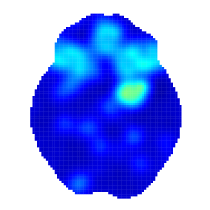

Figure 2 shows the mean posterior of , the average intensity of a working memory study, where , is the intensity for verbal WM studies and is for non-verbal WM studies (mean age and number of participants are set equal equal to the average values in our dataset). We can see that working memory engages several regions of the brain. The regions mostly activated are the frontal orbital cortex (axial slice , left), the insular cortex (, right and , left and right), the precentral gyrus (, left), Broca’s areas ( & , bilateral), the angular gyrus (, left), the superior parietal lobule (, right) and the paracingulate gyrus (, middle).

Our results are qualitatively similar to results obtained by Rottschy et al. (2012) who used the ALE method. However, our model-based approach allows us to derive several quantities of interest along with credible intervals, that cannot be obtained by any of the kernel-based methods. For example, one may calculate the probability of observing at least one focus in a set of voxels, e.g. an ROI or the entire brain. Table LABEL:tab:roi summarises the posterior distribution of , the probability of observing at least one focus in , for several ROIs . A full brain analysis can be found in Appendix D. The division of the brain in ROIs is done according to the Harvard-Oxford atlas (Desikan et al., 2006).